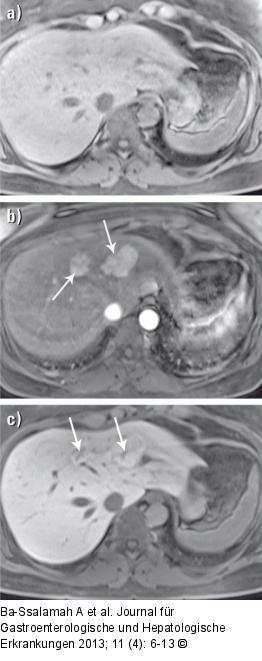

Abbildung 2a-c: MRT-Diagnostik MRT-KM-Anfärbeverhalten bei Fokaler Nodulärer Hyperplasie (FNH): (a) In dem T1-gewichteten Bild ohne Kontrastmittel ist keine fokale Leberläsion zu erkennen, da FNHs meistens ähnliche Signalintensitäten (= Helligkeit) wie das umgebende Lebergewebe aufweisen. (b) Nach KM-Gabe zeigen die 2 nebeneinanderliegenden FNHs ein starkes KM-Enhancement in der arteriellen Phase und sind gut detektierbar. (c) 20 Minuten nach Gabe von Gadoxetat (Primovist®) zeigen die 2 nebeneinanderliegenden FNHs eine ähnliche KM-Aufnahme wie das umgebende Lebergewebe. Es demarkieren sich nun auch die charakteristischen (dunklen) Narben. Dies sind sichere radiologische Merkmale für die Diagnoseerstellung von FNHs. |